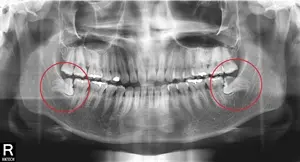

발치 과정은 환자에 따라 다르지만, 일반적으로 ‘파노라마’로 불리는 방사선촬영을 통해 사랑니의 상태를 파악하고 전문의의 판단 하에 발치를 진행하게 된다. 정상적으로 맹출한 경우에는 발치 과정이 비교적 간단하지만, 누워서 자라거나 잇몸 속에 매복되어있는 경우 발치 과정이 복잡해진다. 이런 경우 잇몸을 절개 한 후 사랑니 주변 뼈를 조금 갈아내고 치아를 조각내서 뽑아낸다. 사랑니가 턱뼈 속 하치조신경에 닿아 있거나, 통과하는 경우에는 발치의 난이도가 급격하게 상승하는데, 이 때 에는 구강악안면외과 전문병원이나 대학병원 같은 큰 병원을 방문하는 것이 좋다.

원래의 기능은 다른 어금니와 마찬가지로 음식을 씹어 소화하기 좋은 형태로 만드는 것이나, 현대에 이르러서는 정상적인 위치가 아니라 기형적으로 맹출하는 경우가 많기에 정상적인 기능을 하는 경우는 소수이다. 치아 전부가 매몰된 채로 있는 매복지치, 비스듬하게 또는 수평방향으로 나는 수평지치, 불완전하게 나는 반매복지치 등이 있다.